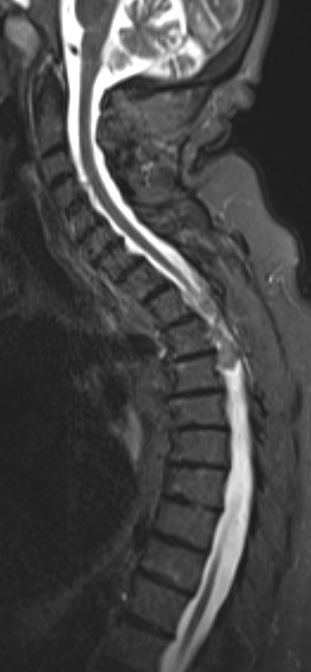

| Rückenmark |

76-jährige Frau mit Rezidiv eines Rückenmarks-Meningeoms. Erstmanifestation vor 17 Jahren. Rezidive von 12, 6 und 3 Jahren jeweils operativ beherrscht. Seit einem Jahr erneut Schmerzen zwischen den Schulterblättern und Druckgefühl im Thoraxbereich. Reduzierter AZ und adipöser EZ. KHK, VHF, Hypertonie, Hypothyreose. Auf Rollator angewiesen. Zunehmende Gangunsicherheit und Kribbeln in den Beinen. Klopfschmerz im Bereich von BWK2-5 stark auslösbar. Die Schmerzen strahlen zeitweise in die Schulterblätter aus. | ![]() | |||||

![]() |

![]() | ||||||